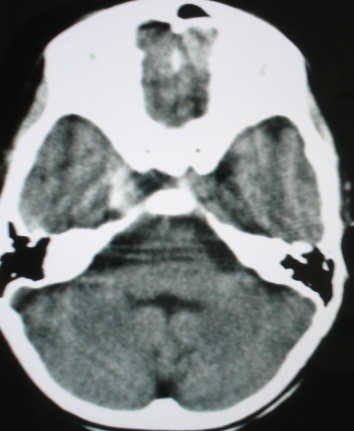

m/8y,右侧眼睑下垂数天,头昏,无呕吐、无外伤史。无搏动性突眼。病人明天来增强。

考虑颈内动脉海绵窦段动脉瘤,建议mri检查。

如此年龄,如此之大的血管瘤实属不多见.还是强化后看看再说吧

不除外右侧海绵窦脑膜瘤,建议增强进一步检查。